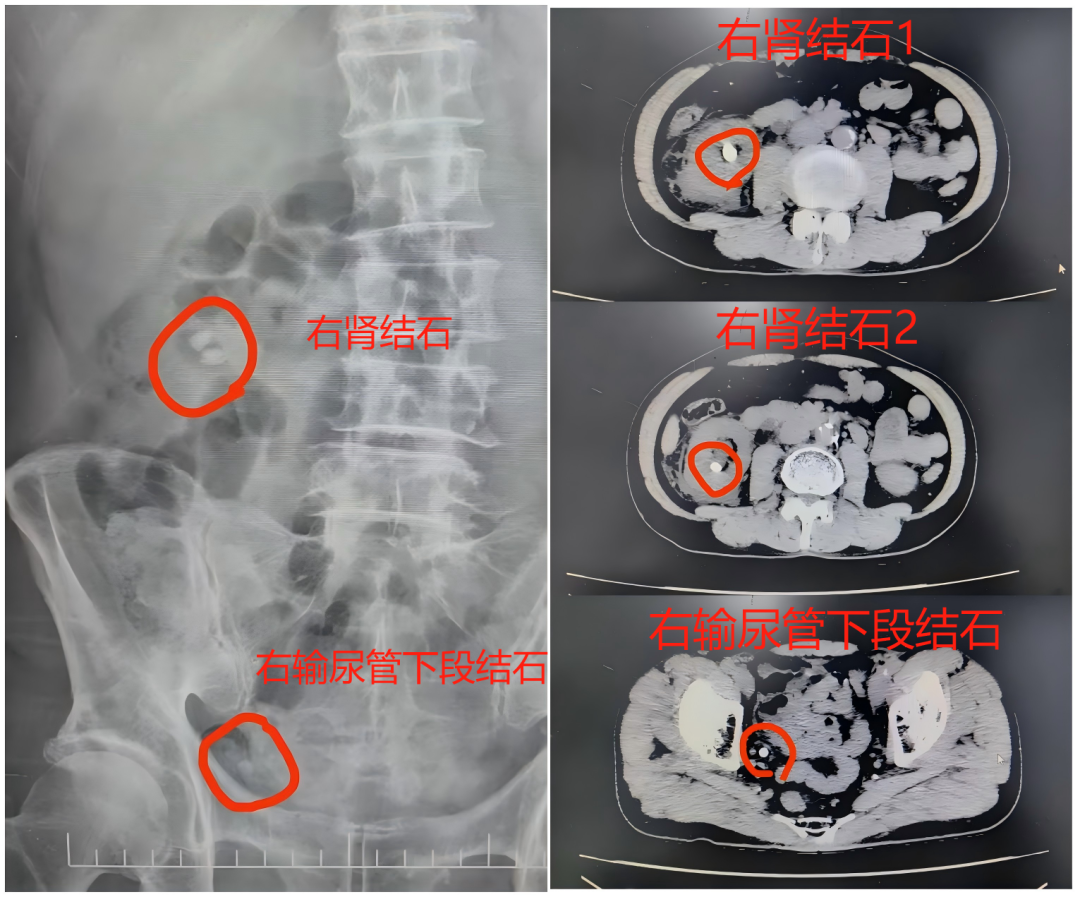

泌尿外科团队详细检查后,陈先生被确诊为右输尿管多发结石伴积水和感染,还有双肾多发结石,较大者超过1.5cm,手术指征明确。